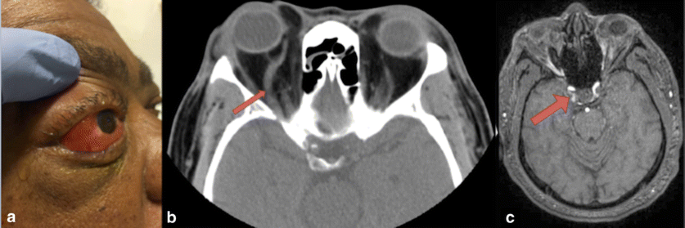

A 56-year-old man presented with subacute injection of his right eye and diplopia. He had no head trauma. His exam demonstrated right eye proptosis, chemosis (Fig. 1a), afferent pupillary defect, abducens nerve palsy (Video, available online), decreased visual acuity, and increased intraocular pressure. Non-contrast CT revealed right superior ophthalmic vein distention (Fig. 1b) suggesting vascular pathology. Non-enhanced MRI demonstrated increased signal intensity in the right cavernous sinus (Fig. 1c) consistent with a carotid cavernous fistula (CCF). Indirect CCF was confirmed by cerebral angiography.

a Demonstrated is right eye proptosis, chemosis, and conjunctival injection. b Non-contrast CT revealed right superior ophthalmic vein distention (arrow) which suggested carotid cavernous fistula. c Non-enhanced MRI revealed asymmetrically increased signal intensity in the right cavernous sinus (arrow) consistent with right carotid cavernous fistula.